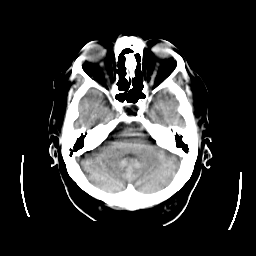

CT Study #2 -- Slice #7